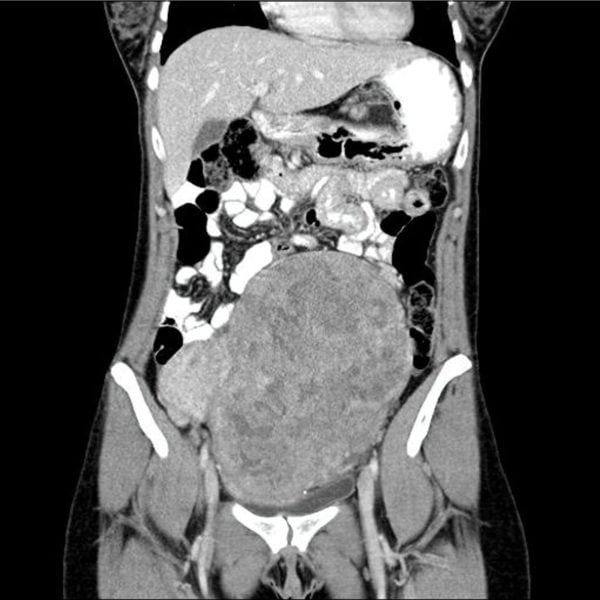

CT/MRT

Myome werden manchmal als Nebenfund entdeckt, wenn aus anderen Gründen eine CT oder eine MRT durchgeführt wurde. Wegen der besseren Gewebespezifität und der fehlenden Strahlenbelastung sollte, wenn überhaupt notwendig, ein MRT durchgeführt werden.